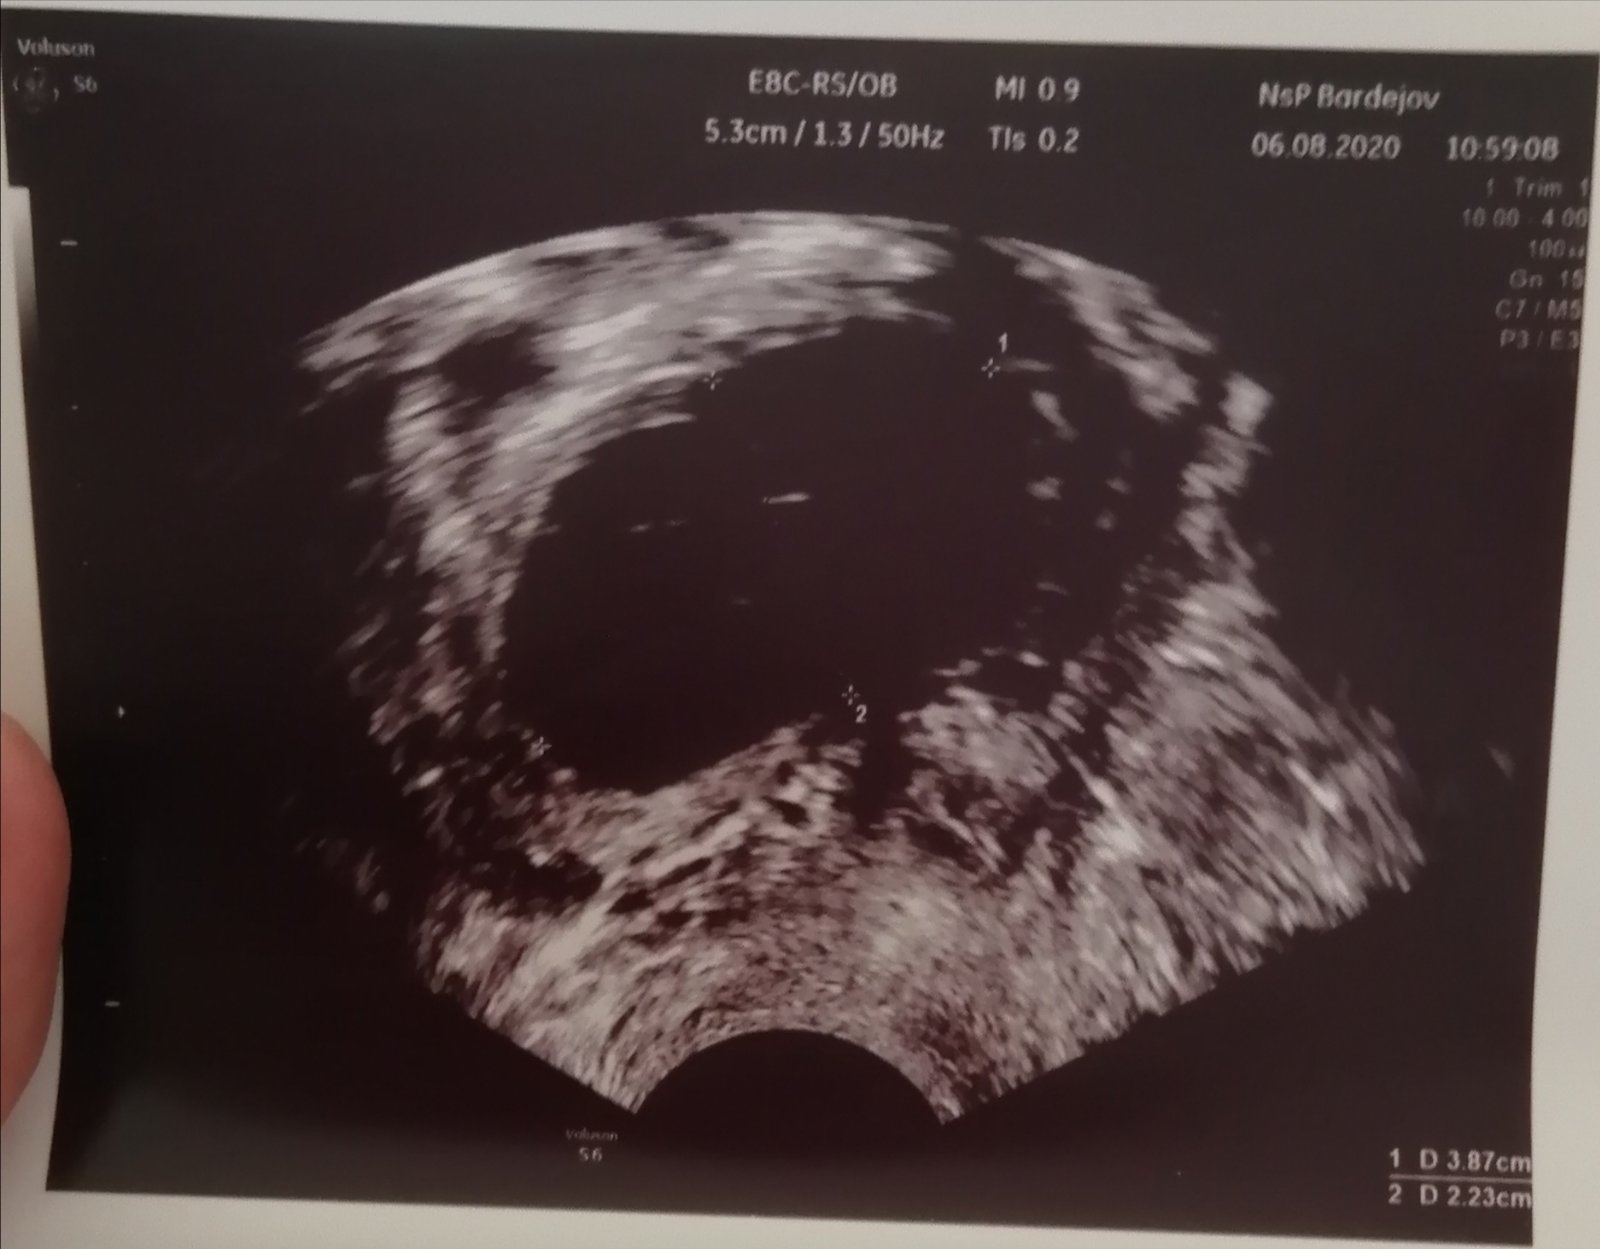

Oplatí sa absolvovať 3D ultrazvuk alebo 4D ultrazvuk?

A ako prebiehajú screeningy v 1. a v 2. trimestri?